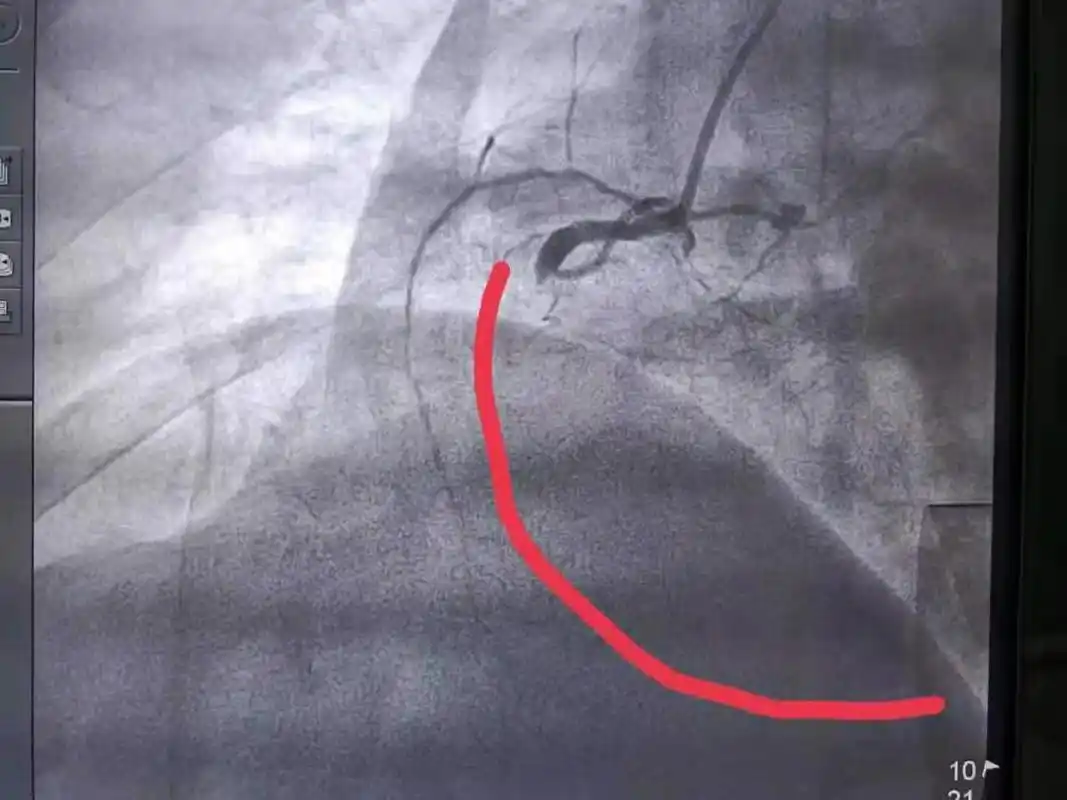

冠脉造影显示老杜的心脏血管多处堵塞,病变

造影显示,右侧血管根部闭塞

急诊冠脉造影示:回旋支近段闭塞.

造影显示,右侧血管根部闭塞支架后血流恢复正常所以造影证实了我们的

术前,术后冠脉造影,血管从完全闭塞到血流畅通